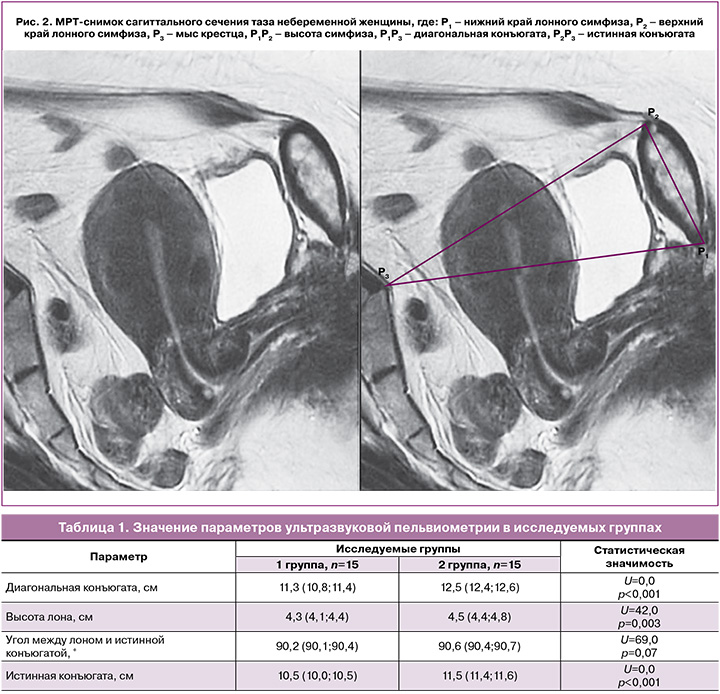

Группы, входящие в структуру I этапа исследования, несмотря на малую численность, статистически значимо отличались по всем изучаемым параметрам, за исключением угла, образованного прямыми, соответствующими высоте лона и истинной конъюгате (табл. 1).

Обращает на себя внимание не столько наличие статистически значимых различий между исследуемыми группами, сколько значение угла между лоном и истинной конъюгатой, приблизительно равное 90° в обеих исследуемых группах. Для подтверждения данной закономерности целесообразным является определение соответствующего угла с помощью МРТ [10]. Однако у беременных женщин проведение МРТ имеет ряд существенных ограничений, описанных ранее. Учитывая относительную динамическую стабильность костного таза, для подтверждения выявленной закономерности достаточно провести оценку соответствующего угла у небеременной женщины. При геометрическом анализе МРТ сагиттального сечения таза небеременной женщины данная закономерность также имеет место: угол, образованный высотой лона и истинной конъюгатой, приблизительно равен 90° (рис. 2).

На рис. 2 представлено схематическое изображение костного таза женщины в сагиттальном сечении и буквами обозначены: P1 – нижний край лонного сочленения, P2 – верхний край лонного сочленения, P3 – мыс крестца. Если соединить все указанные точки на рисунке, то расстояние P1P2 будет соответствовать высоте лонного сочленения, P1P3 – диагональной конъюгате, P2P3 – истинной конъюгате. Угол P1P2P3 близок к значению 90°, что подтверждено результатами ультразвуковой пельвиометрии. Таким образом, треугольник ∆P1P2P3 можно считать прямоугольным, поэтому правомочно использовать теорему Пифагора для расчета стороны P2P3, которая является истинной конъюгатой [11]: